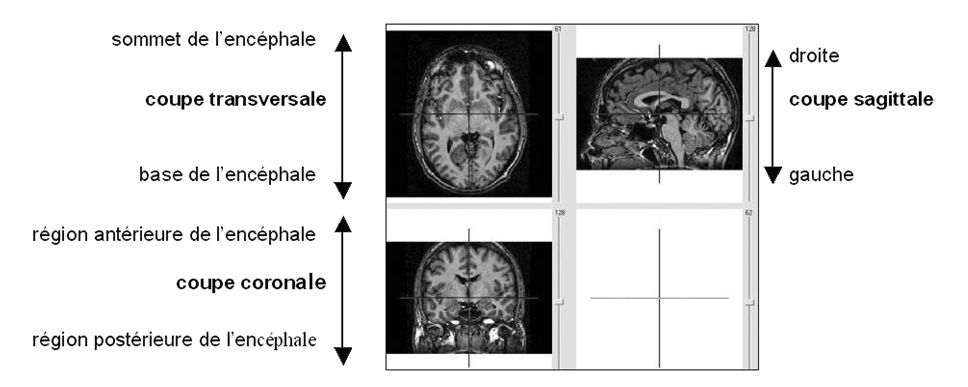

Eduanatomist

Images pour activités première L

4.JPG